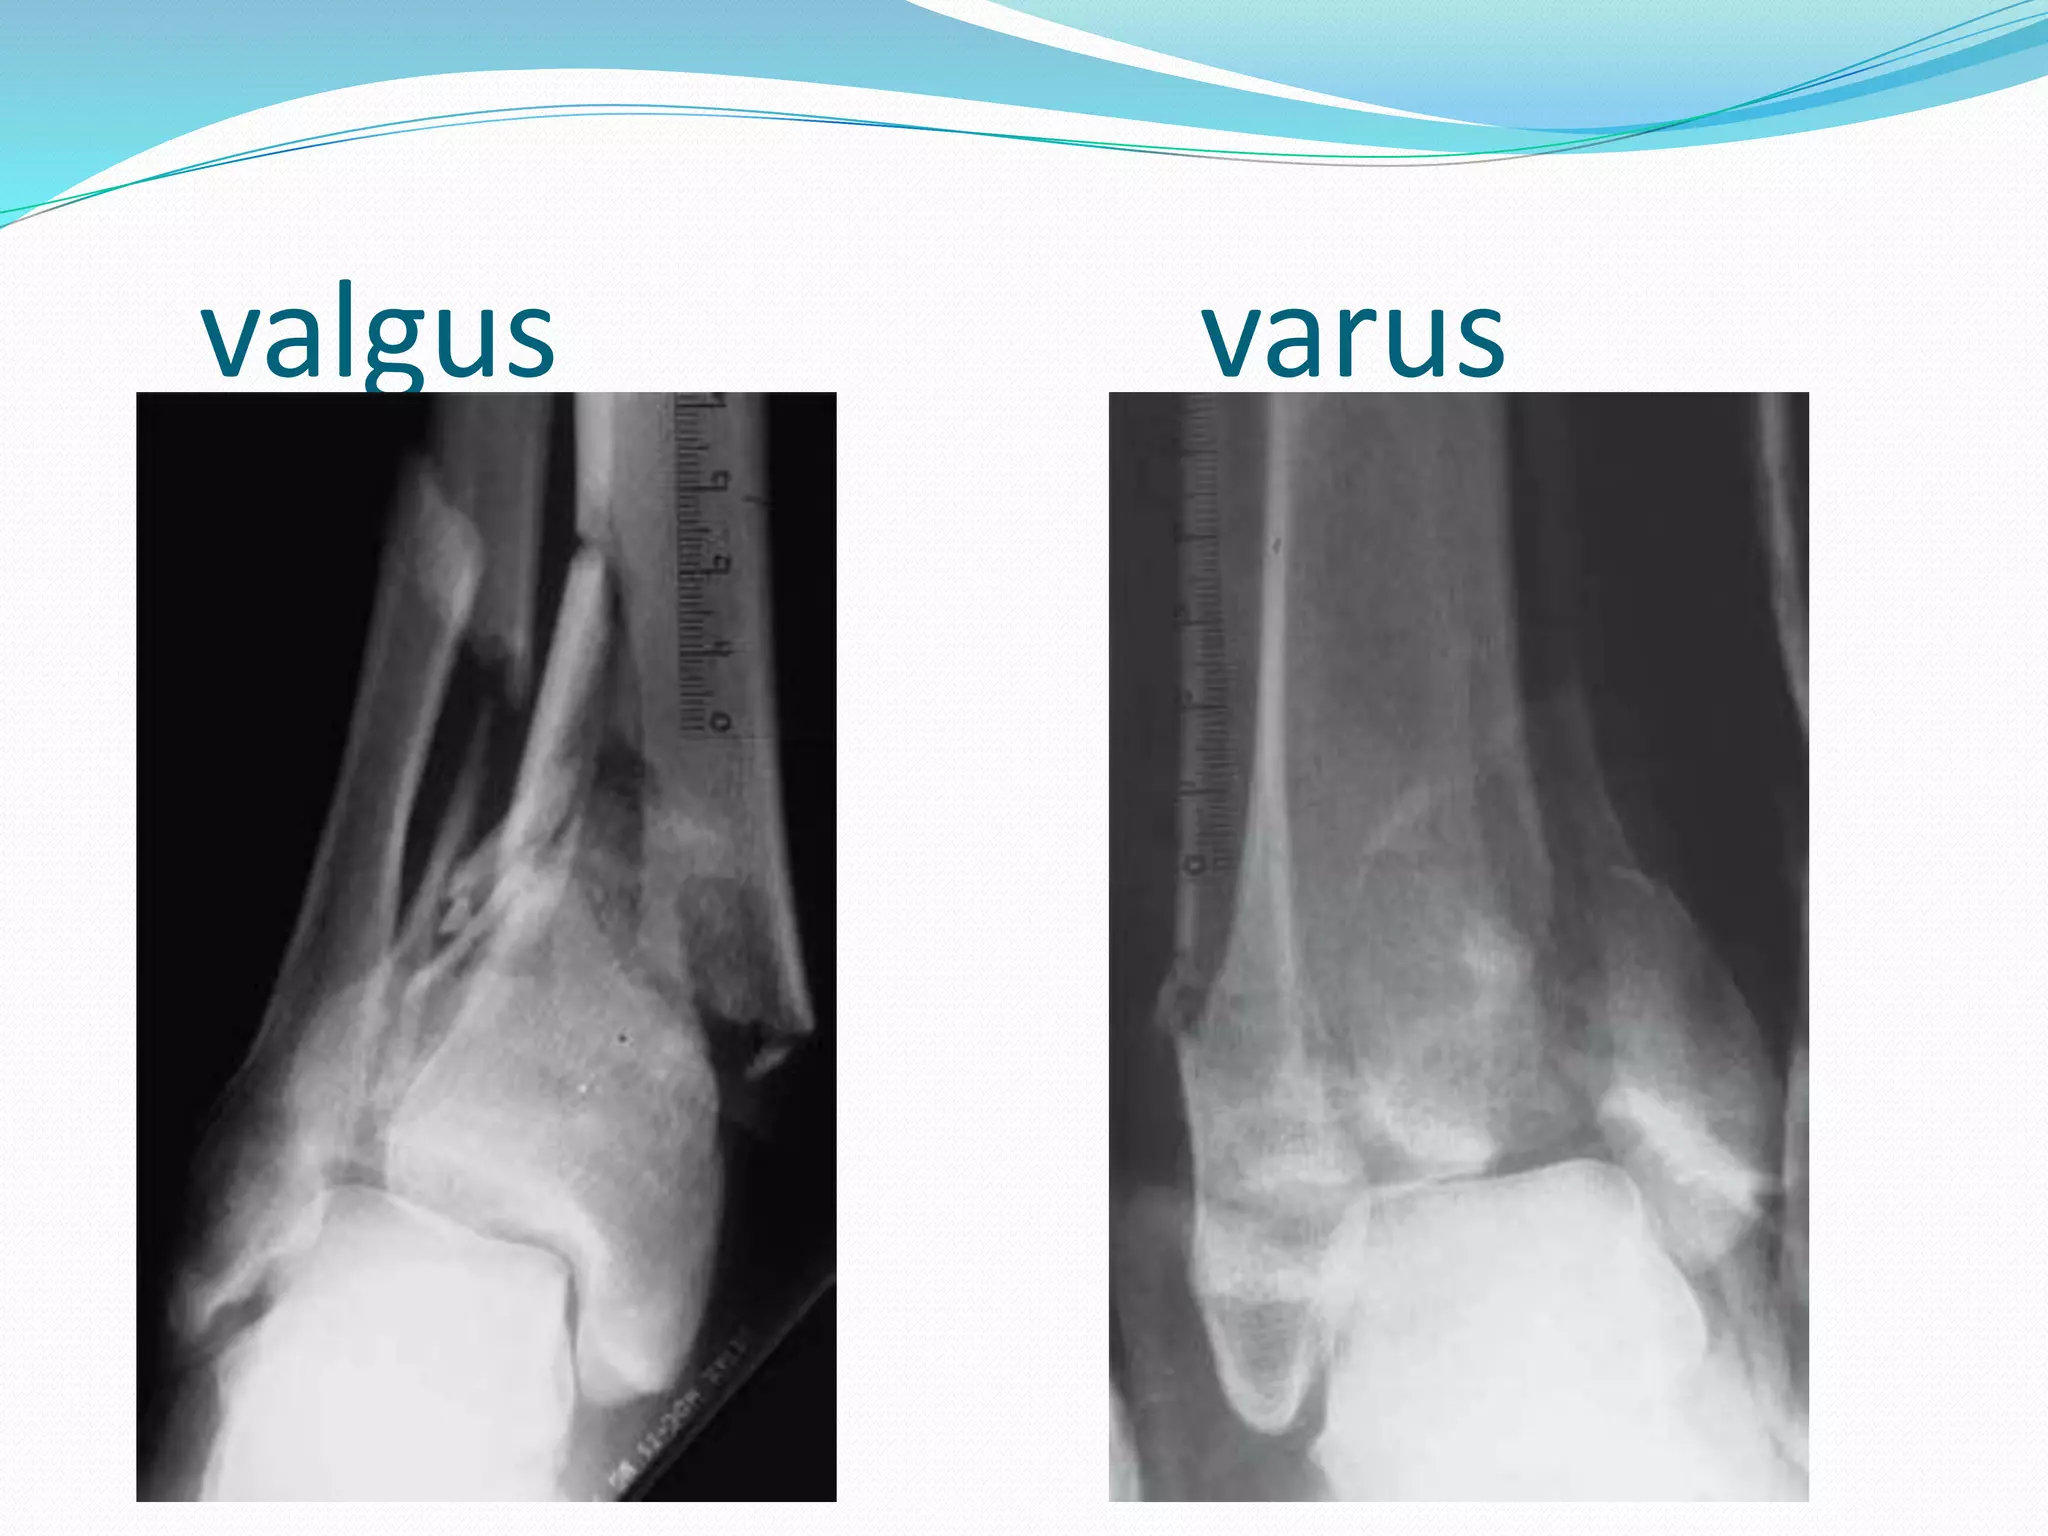

valgus varus